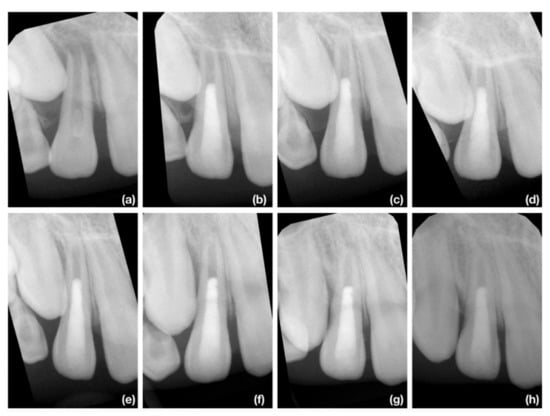

3.2. Radiographic Root Length Change

3.3. Radiographic Root Width Change

3.4. Radiographic Root Area Change